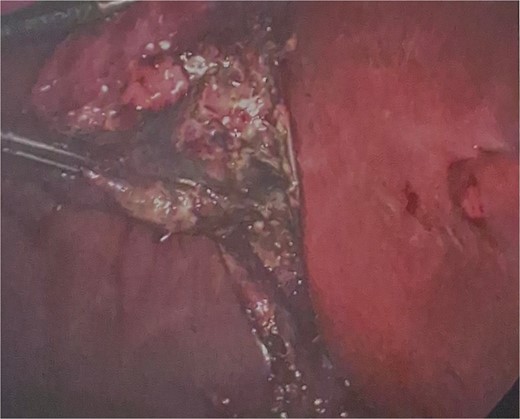

He was brought to theatre for a combined laparoscopic appendicectomy, drainage of peri-appendiceal abscess and cholecystectomy with intraoperative cholangiogram. Intraoperative findings included a 2 cm peri-appendiceal abscess cavity (Fig. 3) in keeping with pre-operative imaging. However, the gallbladder was gangrenous with a possible microperforation sealed by omentum (Fig. 4). Based on the intraoperative appearance, it was difficult to ascertain whether the abscess was due to primary appendicitis or whether the abscess was seeded from the cholecystitis and the appendix had become involved collaterally.